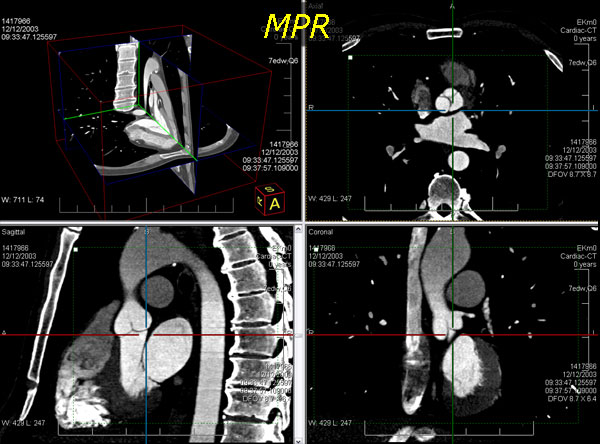

3d volume screenshot

• mpr(多平面重建法)mpr是从二维影像数据堆栈中的任意平面二次重构的二维重定格式图像。在leadtools中,默认将其渲染成三维模型的三种不同正交平面视图。此外,二维和三维正交平面的位置间有一个交互;因此,在任何二维平面上滚动,在对应的三维mpr平面可以表现出来,反之亦然。mpr通常用于检查脊椎的图像,查看椎间盘,这在二维图像中是很难看出来的。三维视图更容易看出脊椎和其他部分的位置关系。